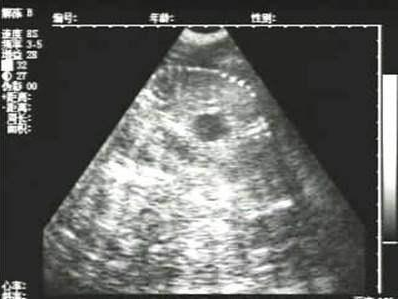

懷孕后期胎兒骨骼圖像

需要注意的是,出現(xiàn)云團狀必須雙側(cè)檢查加以確認.根據(jù)B超機顯示圖我們大致可以判斷孕齡.圖像呈橢圓或者卵圓形大致為30天左右孕齡;圖像呈橢圓形或者卵圓形外,有明顯發(fā)亮骨骼圖像大致為50孕齡左右;圖像囊胚消失,發(fā)亮處隱約可見竹節(jié)狀東西為成型胎兒骨骼,一般為后期80孕齡以后。一般B超機成像會出現(xiàn)三種顏色,白色、黑色、灰色。白色為密度較高的物體,如骨骼或者結(jié)實.黑色一般為液體,包括血液、羊水、組織間隙液體、炎癥病灶等。灰色一般為實質(zhì)性物質(zhì),如肌肉。